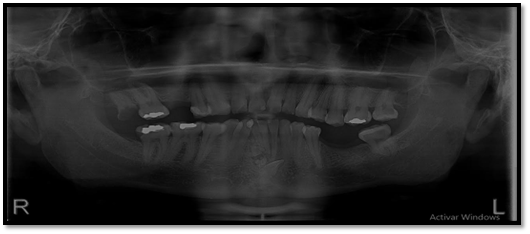

El órgano dentario retenido tiene una dirección mesioangular, sobrepasando la corona la mitad de la línea media. En íntima relación se encuentra las raíces de los órganos dentarios 4.1; 3.1; 3.2 con los dentículos y adicionándose con la relación del órgano dentario retenido esta la raíz del órgano dentario.

Imagen 3. Radiograficas Peiapical.

El diagnóstico y tratamiento oportuno que se debe tener frente a las neoplasias odontogénicas que son frecuentes en la consulta odontológica, y la mayoría de casos pasa desapercibido nos hacen tomar conciencia de lo importante de tratar , guiar a los pacientes que visitan la unidad de atención odontológica Uniandes a realizarse exámenes complementarios, radiográficos panorámicos, periapicales, oclusales que tienen la posibilidad de demostrar una visión más clara de las estructuras dentarias vecinas, previniendo desarrollos o formaciones de neoplasias ya que, las radiografías las intraorales periapicales, oclusales demuestra mayor fidelidad dimensional en comparación a la panorámica detectando oportunamente patologías que son asintomáticas.

En su gran mayoría en la presentación de este caso clínico se puede observar la presencia de una sombra radiopaca que concuerdan con el órgano dentario retenido 4.2.con una imagen mixta con múltiples radiopacidades muy similares a los órganos dentarios que están rodeados de un halo radiolúcido perimetral que son similares descripciones de investigaciones de otros autores.